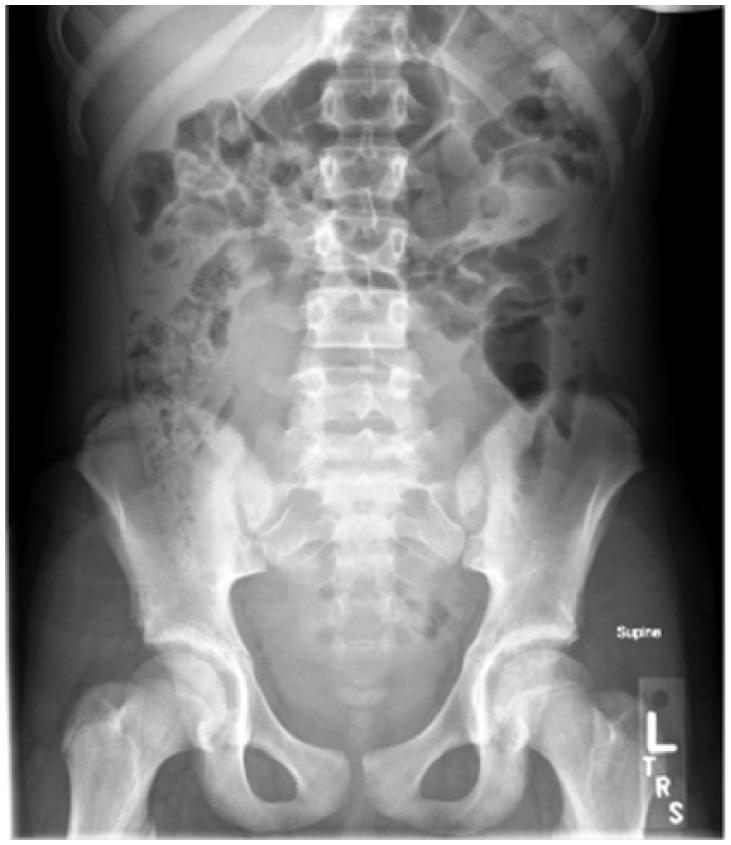

A Variant of Herlyn-Werner-Wunderlich Syndrome Presenting With Acute Abdomen: A Case Report and Review of Literature.